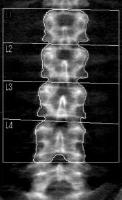

腰椎の測定